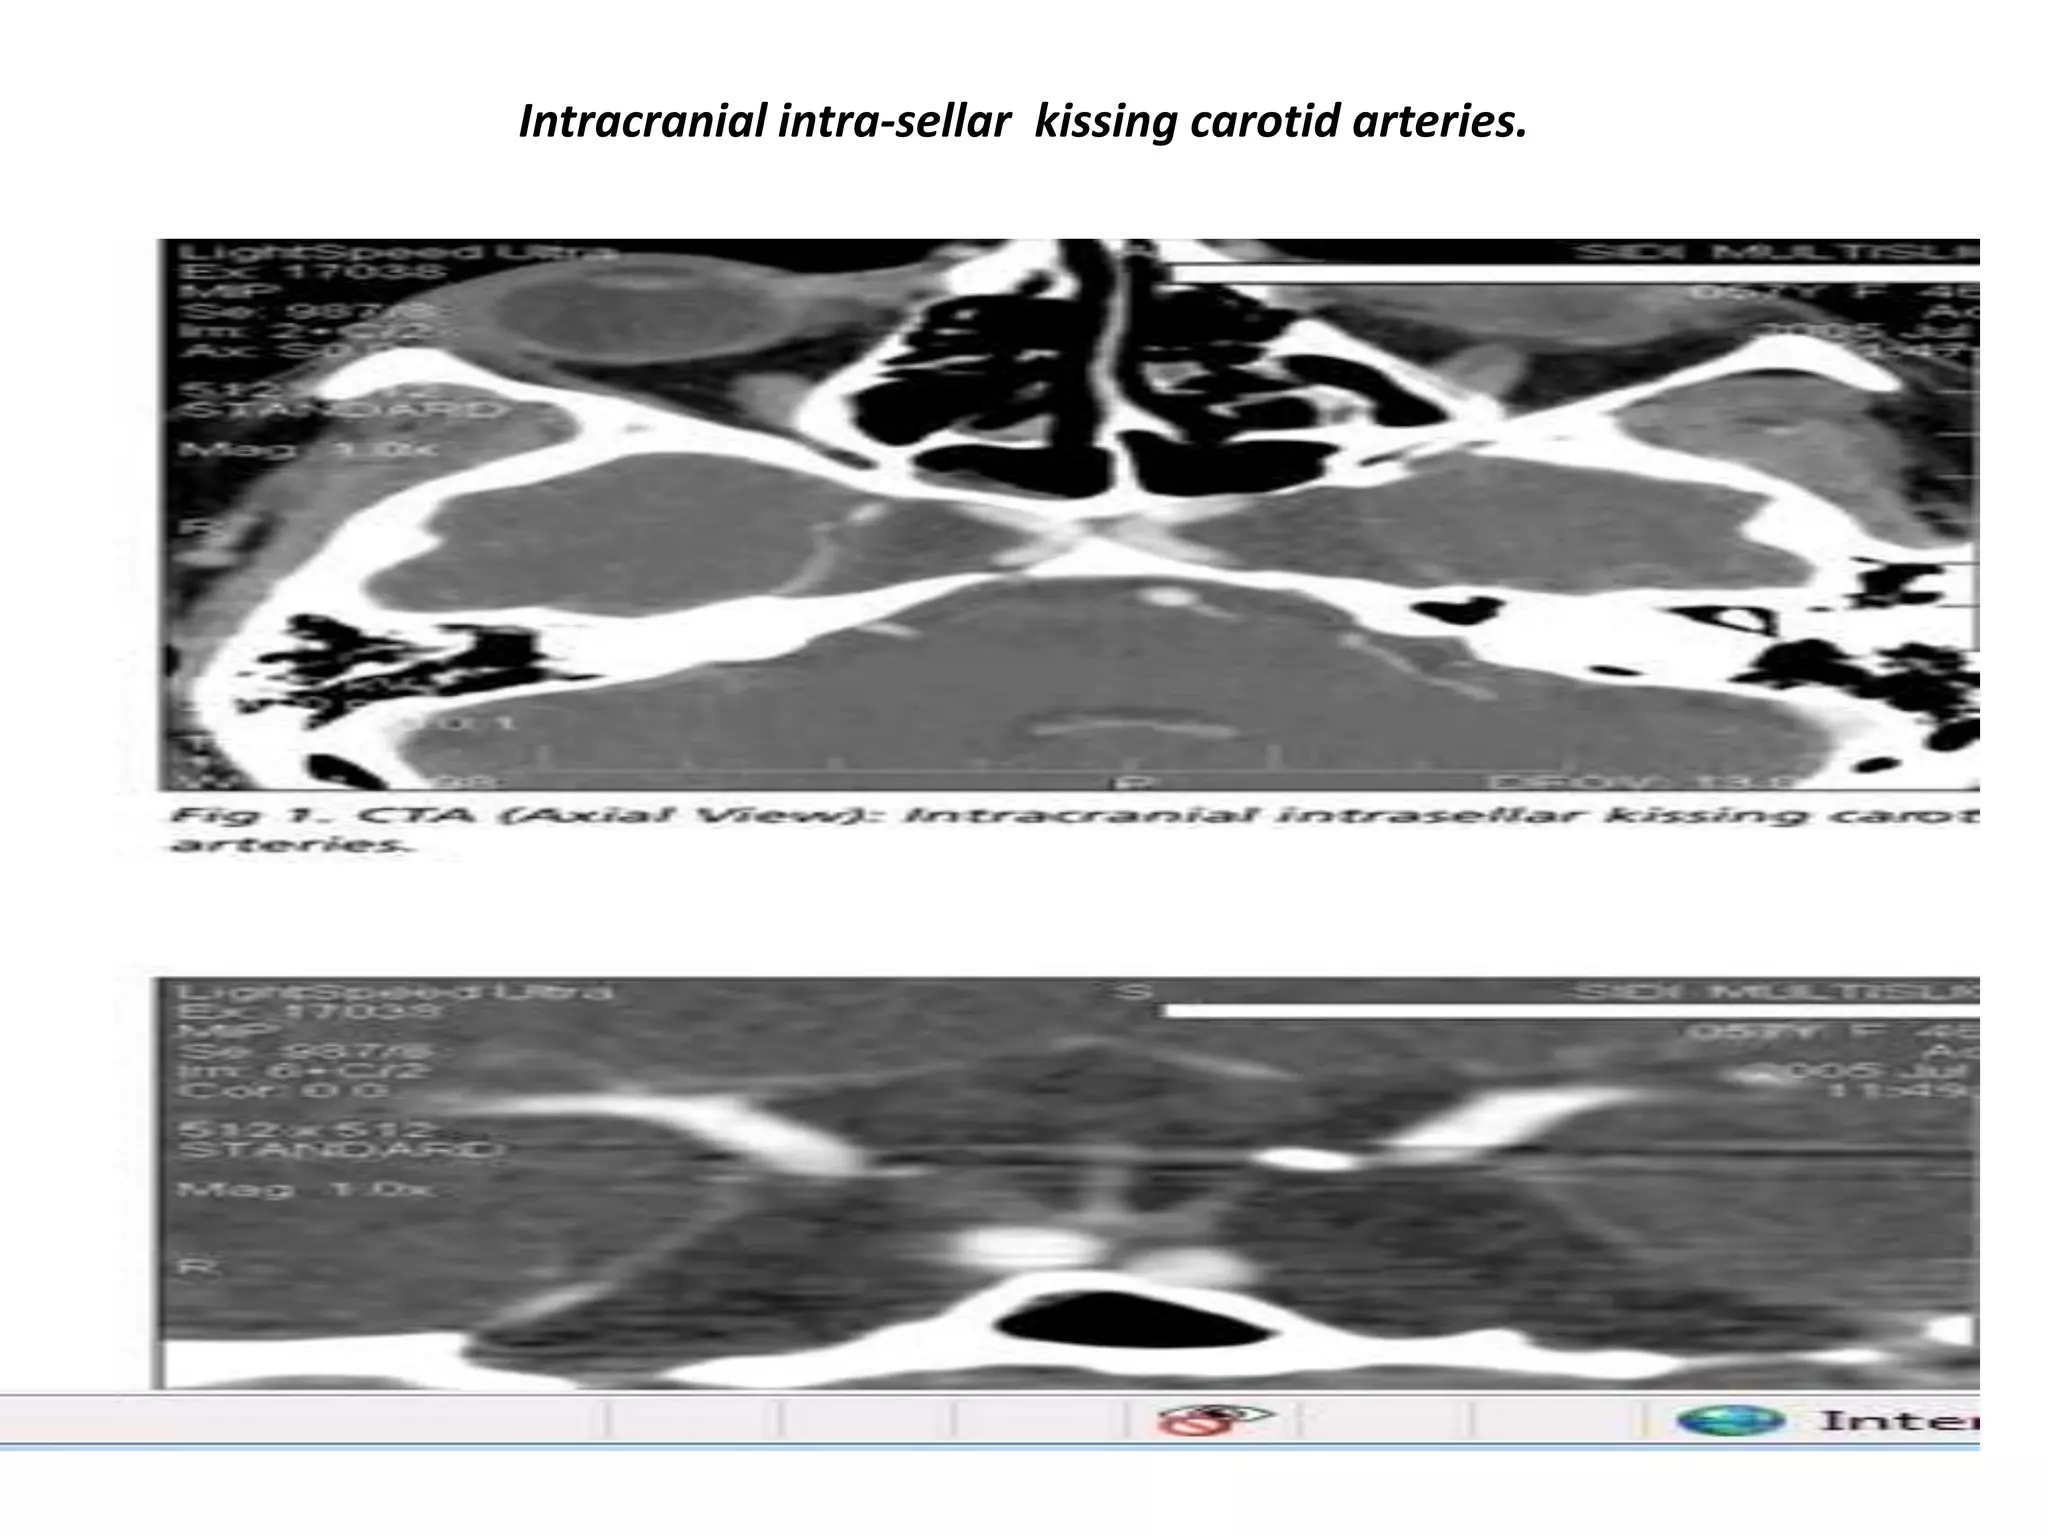

Intracranial intra-sellar kissing carotid arteries.

Carotid artery

A very important structure in this area is the internal carotid artery. It runs a complex anatomic course as it passes through the skull base

shaped like an S on lateral views. It passes through the cavernous sinus. The segment cranial to this is known as the supracavernous

segment. This bifurcates into the anterior cerebral artery, which passes cranially to the optic chiasm, and the middle cerebral artery, which

runs laterally. Aneurysms and ectasias are pathologies that can arise here. One must also be aware of congenital variations in the course

of the internal carotid Sometimes it is very medially positioned and can actually lie in the midline.